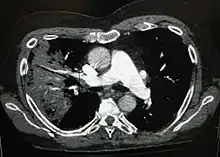

A CT scan can give additional information in indeterminate cases[41] and provide more details in those with an unclear chest radiograph (for example occult pneumonia in chronic obstructive pulmonary disease). They can be used to exclude pulmonary embolism and fungal pneumonia, and detect lung abscesses in those who are not responding to treatments.[40] However, CT scans are more expensive, have a higher dose of radiation, and cannot be done at bedside.[40]